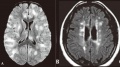

(A) Axial FLAIR sequence showing bilateral, globular, hyperintense lesions in cortical gray matter, centrum semiovale, and deep gray nuclei. (B) Axial FLAIR sequence showing ovoid, periventricular hyperintensities typical of MS plaques. Lee, Y. J. Acute disseminated encephalomyelitis in children: differential diagnosis from multiple sclerosis on the basis of clinical course. Korean J. Pediatr. 54, 234–240 (2011).